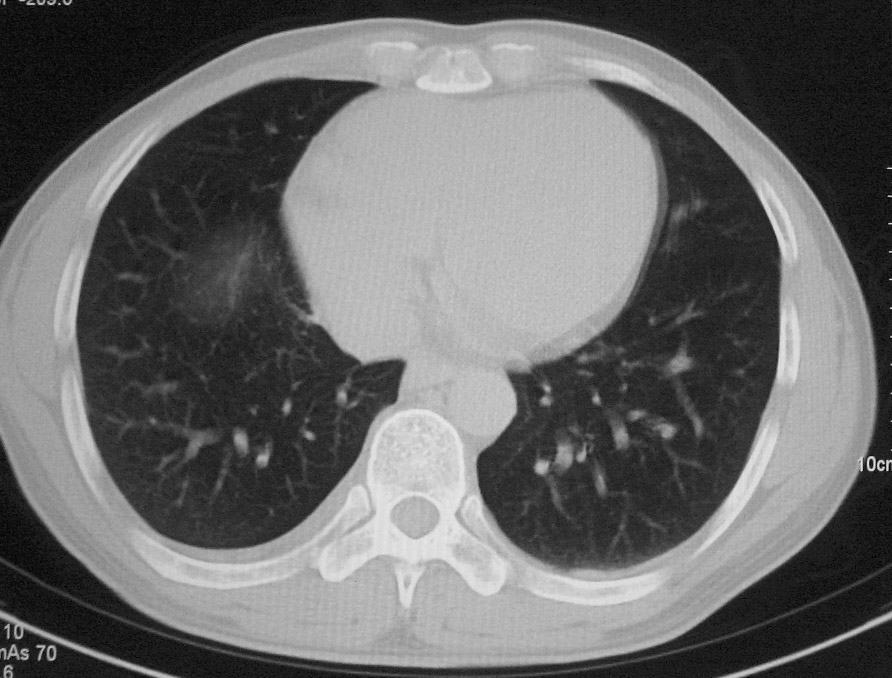

标题: CT5485:[原创]肺部占位请讨论

右肺上叶中央型肺癌并上叶肺不张、纵隔淋巴结肿大

右上叶支气管后壁明显增厚,支持右肺上叶中央型肺癌伴右上叶肺不张、纵隔淋巴结肿大。

右上叶支气管后壁明显增厚,支持右肺上叶中央型肺癌伴右上叶肺不张、纵隔淋巴结肿大。建议支气管镜检查。

右上叶支气管肺癌并右上叶阻塞性不张,右侧少量胸腔积液.

右上叶支气管开口变窄,纵隔见肿大的淋巴结。支持右上叶中心型肺癌并右上叶不张纵隔淋巴结肿大。

右肺上叶中央型肺癌并上叶肺不张、纵隔淋巴结肿大.右侧少量胸腔积液。